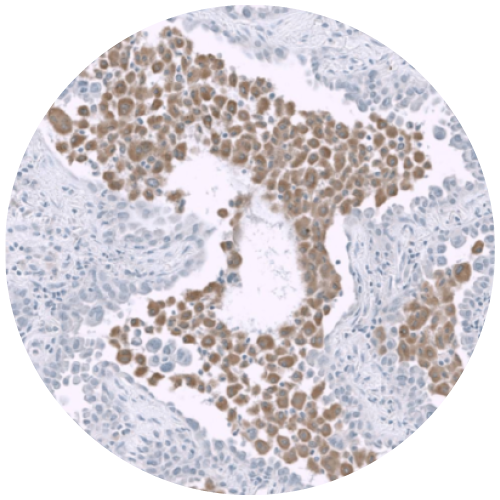

ViewsML uses virtual biomarker staining

in AI-driven diagnostics, discovering deeper

cell-level insights for better patient outcomes

Advantages of Virtual Staining

Multiplexing allows for greater biomarker characterization

Consistent and reproducible immunostaining, every time

May be trained to any biomarker across any disease type and species